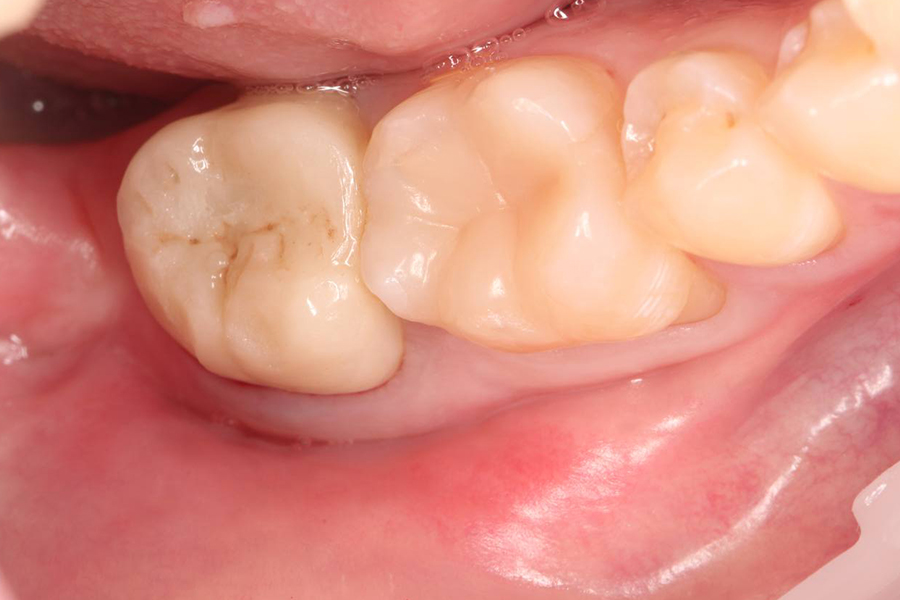

Лечение асимптоматического периодонтита

ЖалобыПлановое перелечивание перед ортодонтическим лечением